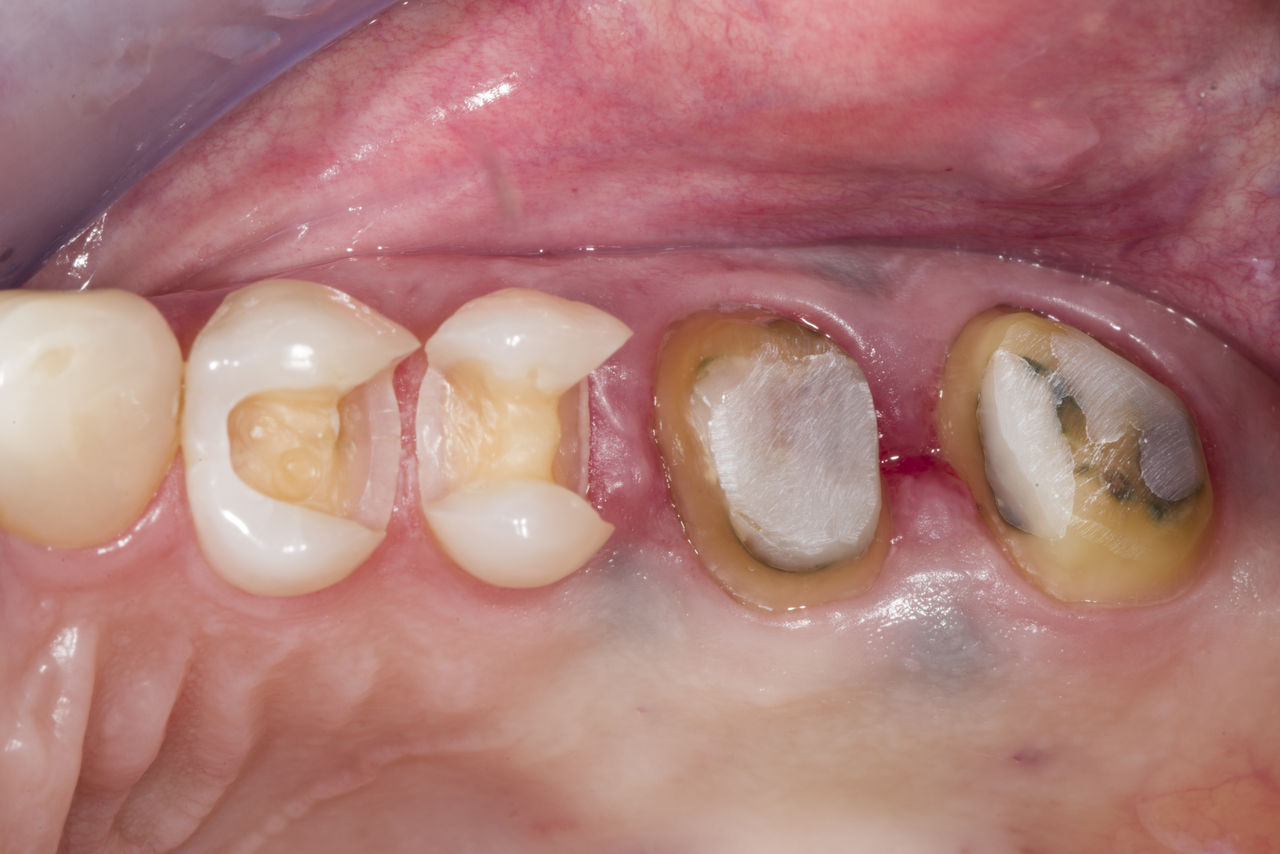

Quadrant rehabilitation

Two CEREC Tessera crowns and two inlays

Within a single visit of four hours the restoration of two crowns and two inlays, which were 15 years old, was carried out. The patient was very pleased with the very good esthetic result.

Before: Insufficient fillings in the second quadrant. The restorations were about 15 years old.

After: Chairside-fabricated crowns made from CEREC Tessera (teeth 26/27). Inlays for teeth 24 and 25 made of composite blocks.